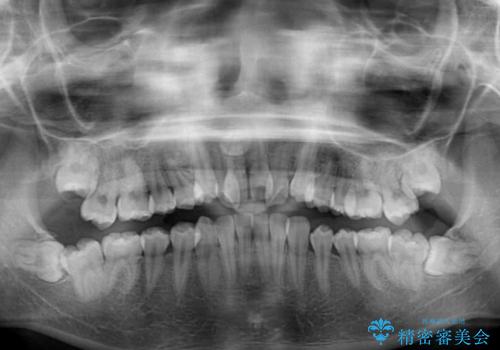

- 骨格的な咬み合わせのズレ、前歯のデコボコとクロスバイトを気にして来院された患者様です。

口元の突出感が若干あり口が閉じにくく、デコボコが強いため、上下左右の小臼歯計4歯を抜歯し、ワイヤー装置による矯正治療を行うこととしました。

また、舌の突出癖が強く、下顎前歯が前方に押し広げられる可能性が高いため、舌癖の改善を継続的に行うよう指示しました。

治療中に舌の突出癖が改善されず、下顎前歯が著しく前方に突出して反対咬合となってしまう局面がありました。

アンカースクリューを使用しながら舌癖の改善を図り、何とか咬み合わせを改善することができました。